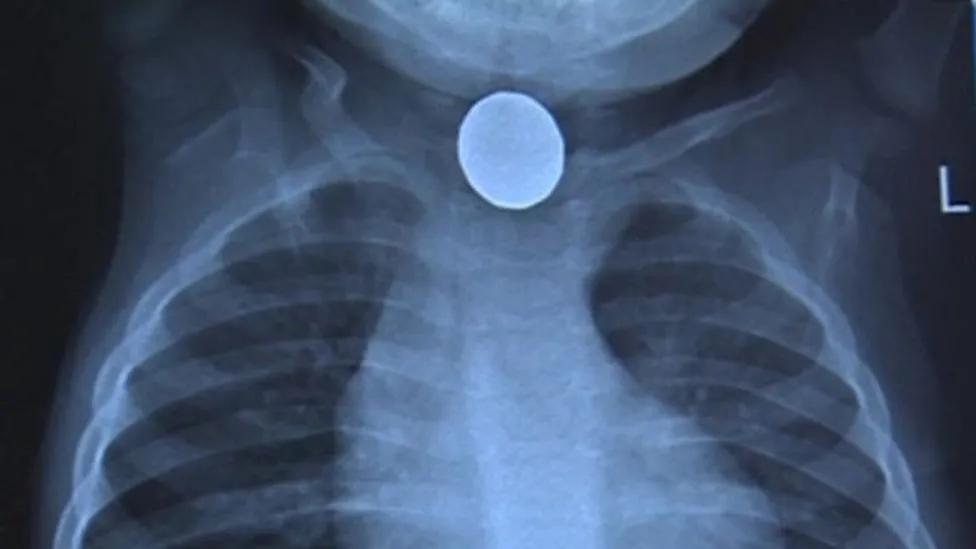

最后医生终于发现了真正的病因—— 让休伊生命垂危的竟然是一颗小小的纽扣电池,它死死地卡住在休伊的食道里。

而其产生的酸已经把小休伊的心脏烧出了一个硬币大小的洞,医生表示这个伤恐怕永远不会恢复。